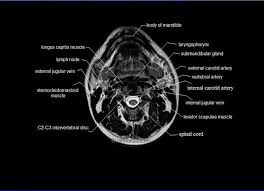

10 rectus abdominus muscle this muscle is consider. There are around 650 skeletal muscles within the typical human body. Muscle movements, types, and names. This image is titled back muscles ct anatomy and is attached to our article about best back muscles training exercises. Scientific studies using sophisticated tools such as electromyography (emg) and. The muscles of your back are complex and work together to provide support, movement, and stability. The superficial back muscles are covered by skin, subcutaneous connective tissue and a layer of fat. Memorize all the muscle facts with the help of muscle cheat sheets.

To build the back optimally, you should know the major muscles, their actions, and which exercises build muscles best. The muscles of the back are a group of strong, paired muscles that lie on the posterior aspect of the trunk. Since this area bears much of your weight and stress, it is the most likely part of the back to become injured. Since learning anatomy is not your primary objective, this is a conceptual view of the the muscles in your upper back are called the trapezius and rhomboids rest underneath your traps. Along it are easily palpable spinous processes by palpation of the cervical vii and all lying. This image is titled back muscles ct anatomy and is attached to our article about best back muscles training exercises. The superficial back muscles are the muscles found just under the skin. Learn about anatomy back muscles with free interactive flashcards.